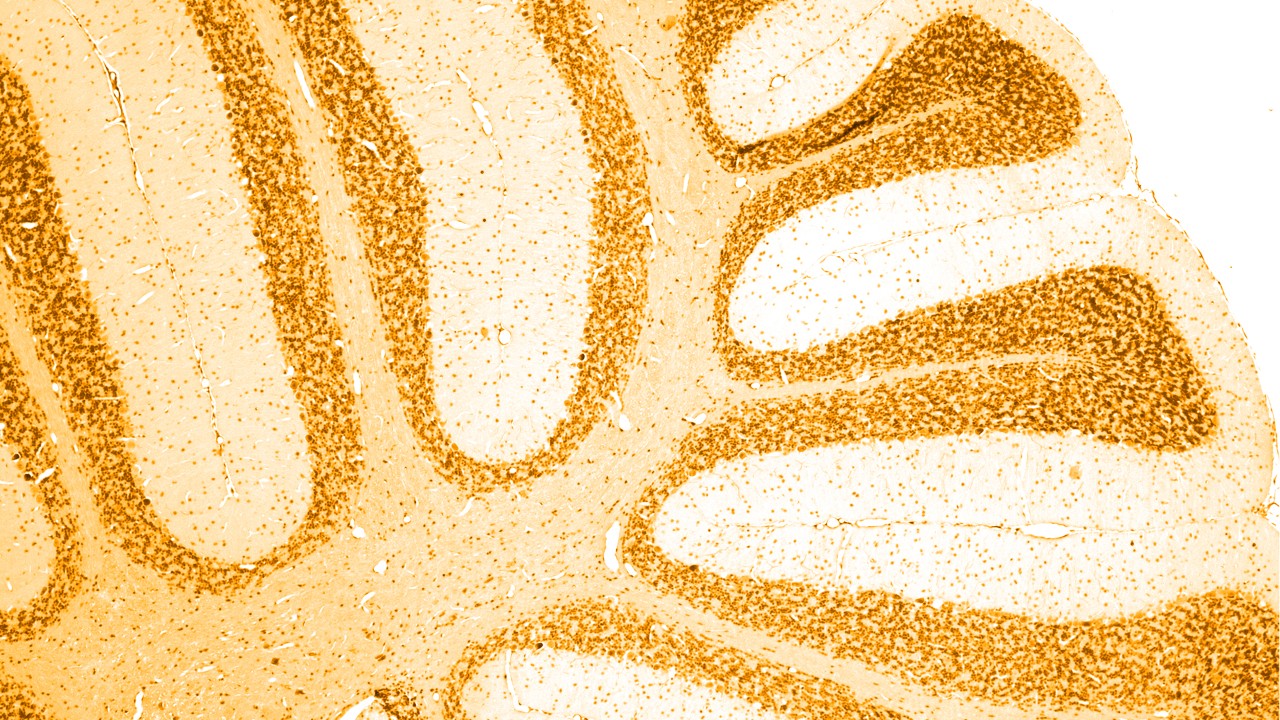

Es gibt viele verschiedene Ursachen für Demenz, von denen die häufigste die Alzheimer-Krankheit ist. Hier finden sich im Gehirn bestimmte Ablagerungen, sogenannte „Amyloid-Plaques“ und „Tau-Bündel“. Auch bei bestimmten anderen Demenzerkrankungen kommt es zu dieser nicht normalen Ansammlung von Tau-Proteinen im Gehirn; deshalb werden sie auch zusammenfassend als „Tauopathien“ bezeichnet.